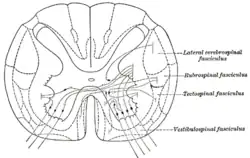

Der Ausdruck Commissura anterior wird auch in Verbindung mit dem Rückenmark verwendet, für Strukturen nahe dessen Zentralkanal. Als Commissura alba anterior[2] wird ein Teil der vorderen Weißen Substanz nächst der Medianfurche bezeichnet, der auf Segmentebene kreuzende Axone führt. Hier verlaufen auch Fasern von Strangzellen, beispielsweise der – nach Umschaltung von Nozizeptoren auf sie – sekundär-afferenten Neuronen im Hinterhorn, die zum Tractus spinothalamicus lateralis auf der anderen Segmentseite hinüberkreuzen. Des Weiteren kreuzen hier segmental Fasern des Tractus corticospinalis anterior vor der Umschaltung auf α-Motoneurone.

Der zwischen der Commissura alba anterior und dem Zentralkanal gelegene Bereich Grauer Substanz wird Commissura grisea anterior[2] genannt. Er zählt zum Eigenapparat des Rückenmarks und enthält Nervenzellkörper und -fortsätze von Binnenzellen, auch Neuriten der Kommissurzellen.